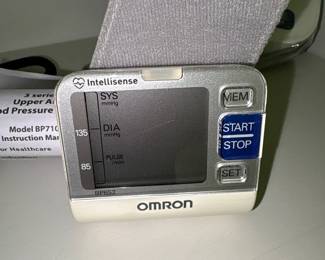

Collectibles